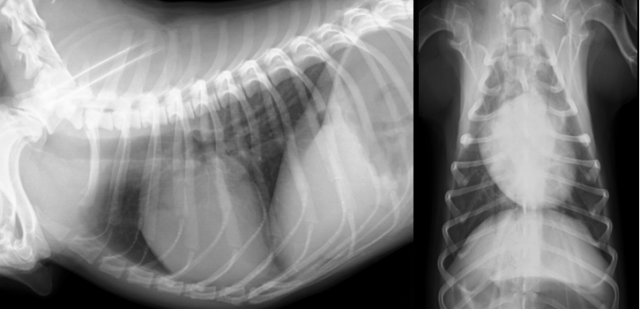

🔍 画像検査で見えた「肺炎」のサイン

レントゲン検査: 肺の前葉〜中葉の腹側(胸の下側)が白く写っていました。これは、重力の影響で誤嚥した内容物が溜まりやすい典型的な部位です。

🏥治療の経過と回復

入院治療の結果、幸いにも白血球数やCRP値は正常化し、レントゲン上の白い影も消失しました。酸素がなくても自力で安定して呼吸ができるようになったため、無事に退院となりました